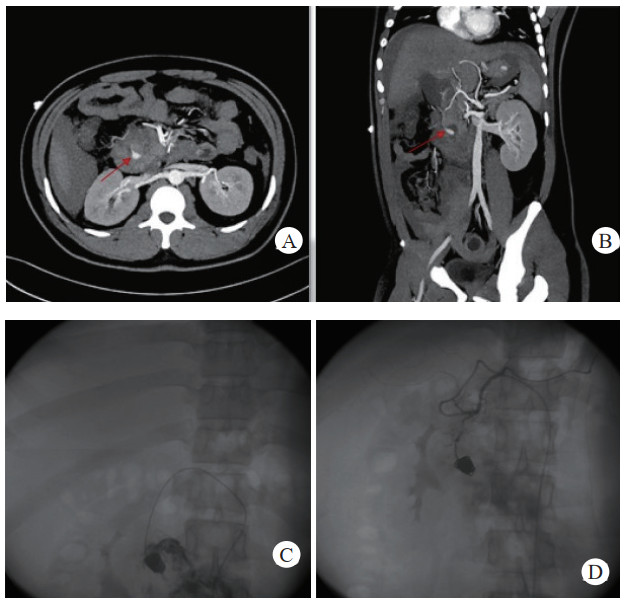

治疗后随诊复查CT显示,患者载瘤动脉及瘤腔内可见栓塞弹簧圈,血肿、假性动脉瘤瘤体体积明显缩小,未见血管再通与假性动脉瘤破裂,见图 2(病例2)。

| 注:图 2病例2 A为患者术前CT增强扫描,示胰腺炎影像,腹腔内见一血肿影,脾动脉起始段可见一瘤样扩张,内见对比剂填充;B、C分别为患者术后3 d及术后1个月复查CT增强示,血肿较前减小,原瘤样扩张处可见弹簧圈影及未见对比剂外溢 图 2 病例2术前、术后CT平扫及增强 |